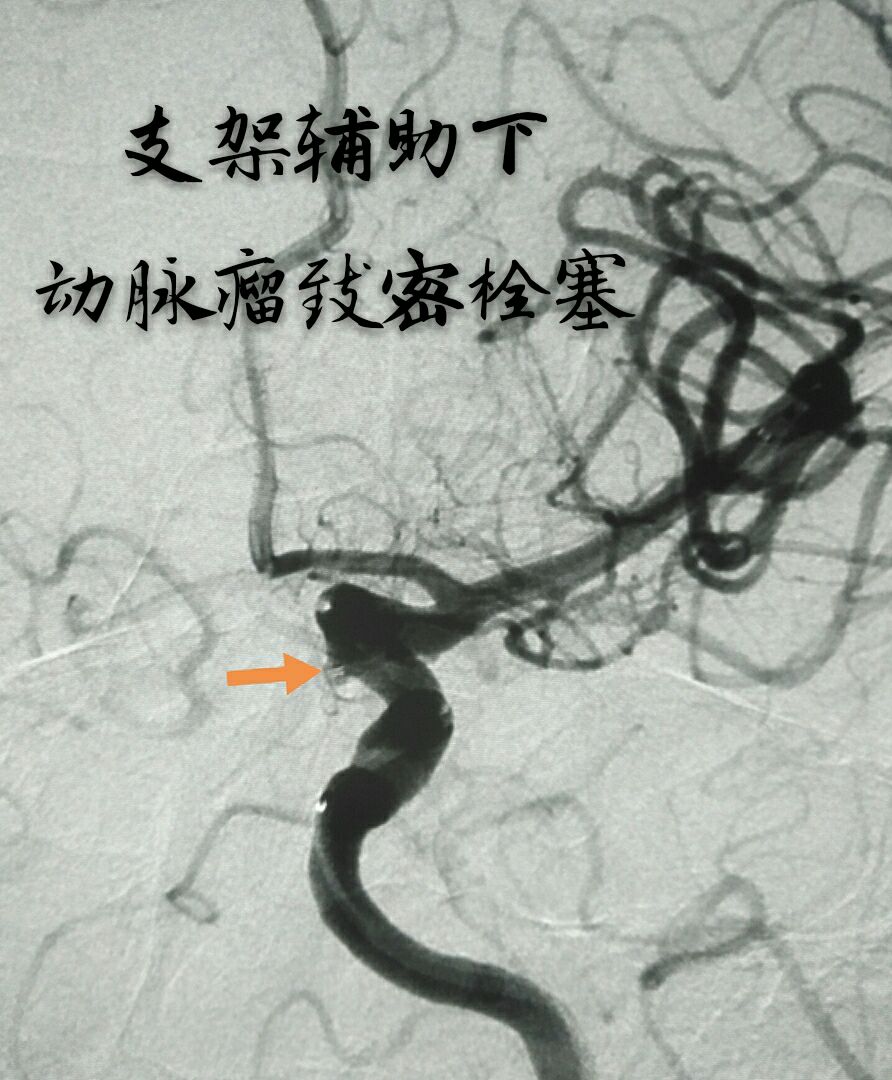

病例十:老年男性患者,间断性头痛1年,DSA示左侧颈内动脉后交通段动脉瘤,后交通动脉从瘤颈部发出

最终动脉瘤致密栓塞,载瘤动脉及后交通动脉通畅